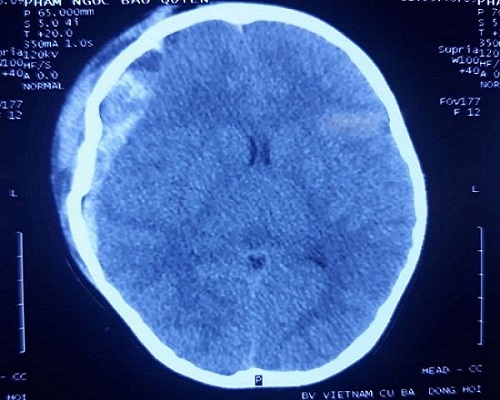

Hình chụp CT sọ não của bệnh nhi - Ảnh: Gia đình Việt Nam |

Gia đình cho biết bé trèo cầu thang, không may trượt chân ngã xuống nền đá hoa, sau ngã cháu bị đau đầu và sưng vùng trán, người thân vội vã đưa cháu đi cấp cứu. Qua thăm khám và chụp X- quang, chụp CT sọ não, các các bác sĩ phát hiện cháu bị vỡ xương trán và thái dương phải, khối máu tụ ngoài và dưới màng cứng vùng thái dương phải, gãy xương đòn phải.

Bác sĩ CKII Nguyễn Văn Mận, Trưởng khoa ngoại thần kinh, cho biết cháu bé bị chấn thương sọ não nặng, diễn biến nhanh. Sau khi ngã cháu vẫn tỉnh táo hoàn toàn, chụp CT sọ não phát hiện một ít máu tụ, chưa có chỉ định phẫu thuật, nhưng chưa đầy một tiếng sau, cháu rơi vào hôn mê. Kết quả chụp CT lại thì thấy lượng máu chảy tăng nhanh.

"Nếu không nhanh chóng phẫu thuật sẽ nguy hiểm đến tính mạng của bé hoặc để lại nhiều di chứng nặng nề", bác sĩ Mận cho biết.

Các bác sĩ đã tiến hành phẫu thuật cấp cứu lấy máu tụ và đặt lại xương vỡ cho bệnh nhi. Hiện cháu đã tỉnh táo, tiếp xúc tốt, ăn được cháo, tay chân không yếu liệt và đang được chăm sóc tại bệnh viện.